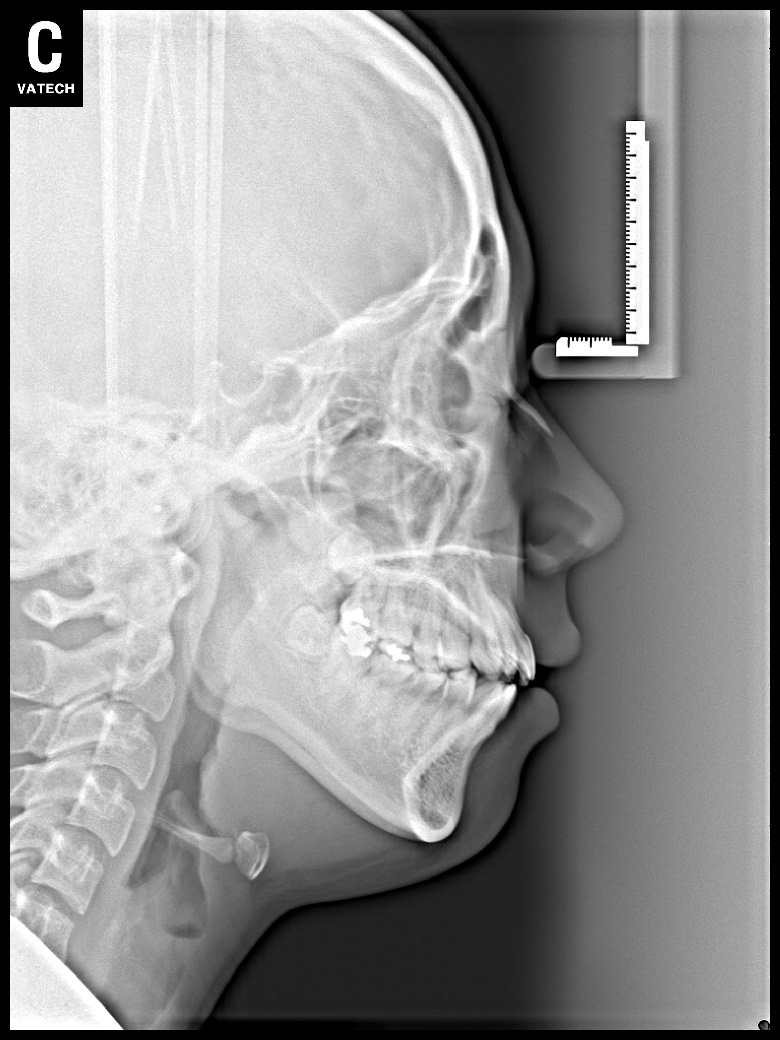

치료 전 사진입니다.